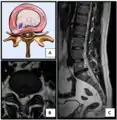

Nucleus herniating through tear in annulus (with MRI)[9]

- Magnetic resonance imaging is the gold standard study for confirming a suspected LDH. With a diagnostic accuracy of 97%, it is the most sensitive study to visualize a herniated disc due to its significant ability in soft tissue visualization. MRI also has higher inter-observer reliability than other imaging modalities. It suggests disc herniation when it shows an increased T2-weighted signal at the posterior 10% of the disc. Degenerative disc diseases have shown a correlation with Modic type 1 changes. When evaluating for postoperative lumbar radiculopathies, the recommendation is that the MRI is performed with contrast unless otherwise contraindicated. MRI is more effective than CT in distinguishing inflammatory, malignant, or inflammatory etiologies of LDH. It is indicated relatively early in the course of evaluation (<8 weeks) when the patient presents with relative indications like significant pain, neurological motor deficits, and cauda equina syndrome. Diffusion tensor imaging is a type of MRI sequence used for detecting microstructural changes in the nerve root. It may be beneficial in understanding the changes that occur after herniated lumbar disc compresses a nerve root, and might help in differentiating the patients that need surgical intervention. In patients with a high suspicion of radiculopathy due to lumbar disc herniation, yet the MRI is equivocal or negative, nerve conduction studies are indicated.[44] T2-weighted images allow for clear visualization of protruded disc material in the spinal canal.

MRI scan of cervical disc herniation between C5 and C6 vertebrae

MRI scan of large herniation (on the right) of the disc between L4 and L5 vertebrae

Example of a herniated disc at L5–S1 in the lumbar spine